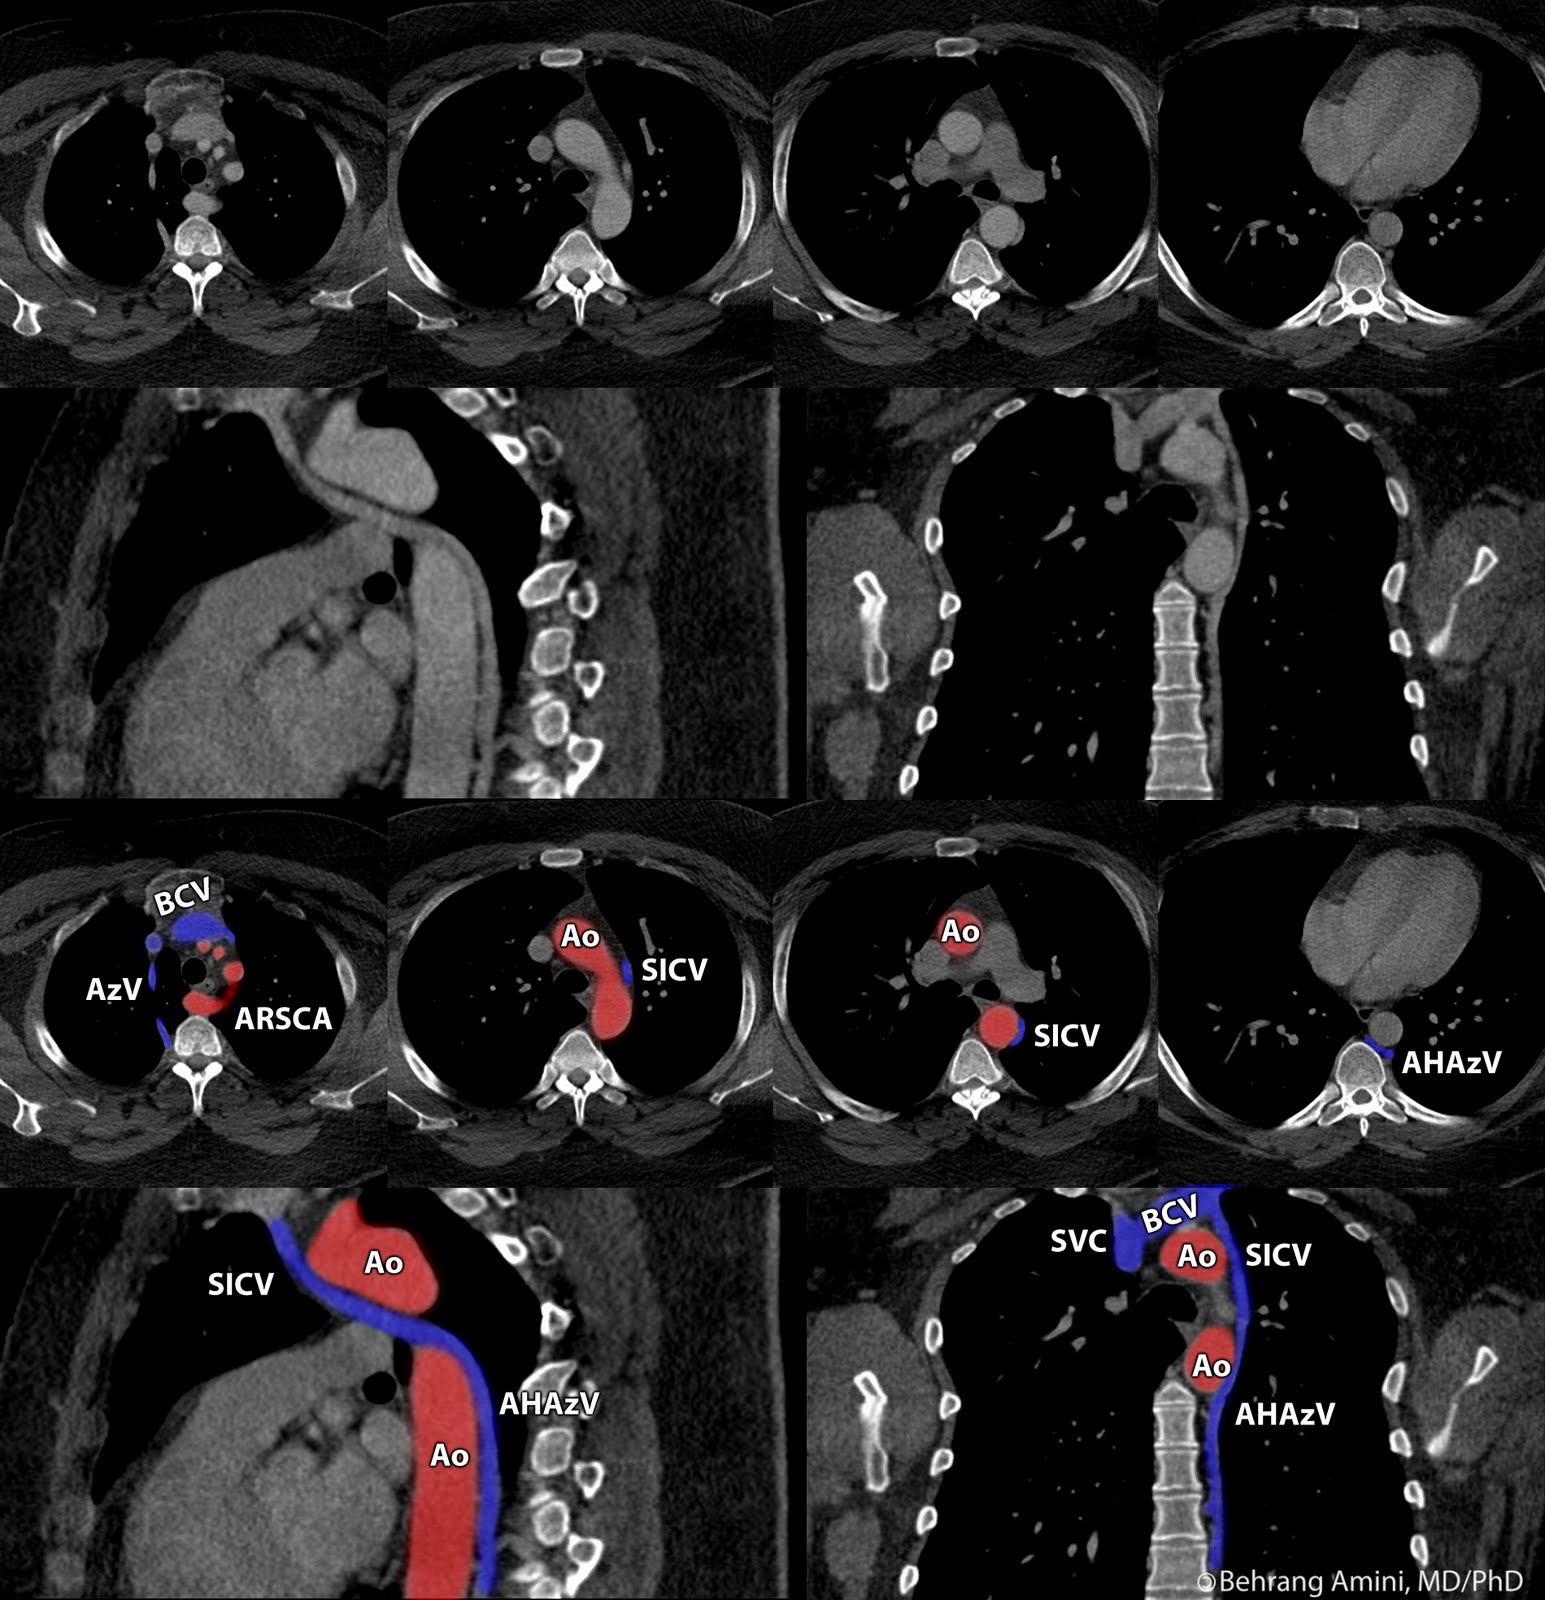

Roentgen Ray Reader Drainage of the Accessory Hemiazygos Vein into the What Are Accessory Hemiazygos Vein Web the accessory hemiazygos vein, or superior hemiazygos vein, courses through the posterior mediastinum, receiving a couple of tributaries along. It is formed by the union of. Web the hemiazygos vein is the asymmetric counterpart to the azygos vein and forms part of the azygos venous. Web azygous vein (ventral view) the hemiazygos vein mirrors the lower part of the. What Are Accessory Hemiazygos Vein.